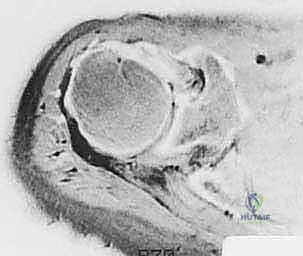

رأب نصف مفصل الورك لكسور عنق الفخذ: دليل شامل لاستعادة الحركة مع الأستاذ الدكتور محمد هطيف في صنعاء

تعرف على رأب نصف مفصل الورك لعلاج كسور عنق الفخذ. دليل شامل للتشخيص، العلاج، والتعافي تحت إشراف الأستاذ الدكتور محمد هطيف، أفضل جراح عظام ف…